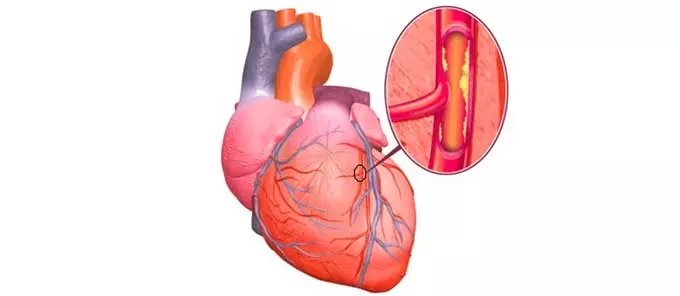

При каких болезнях назначается прием медикамента

Кординорм имеет следующие показания к применению:

- Гипертония.

- Сердечная ишемия, сопровождающаяся проявлением аритмии либо тахикардии.

- Сердечные нарушения хронического течения.

Медикамент используется не только для лечения, а и с целью предотвращения этих недугов в качестве самостоятельного лекарства либо в комплексе с другими средствами.

Влияние Кординорма на сердечно-сосудистую систему и артериальные показатели

При кардиологических заболеваниях сердце и кровеносные сосуды функционируют некорректно, что ведет к усугублению клинической ситуации и зачастую к самым непредсказуемым последствиям, к примеру:

- Тахикардия.

- Гипертонический криз.

- Увеличение нагрузки на миокард.

- Недостаточность сердца.

Предупредить либо облегчить эти и другие патологические проявления помогает Кординорм:

- Активное вещество препарата поддерживает качество и количественный показатель кровяной жидкости.

- Приводит в норму уровень кровяного давления в случае его повышения.

- Уменьшает синтез кальция, тем самым содействуя расширению просвета сосудов и устраняя сосудистый спазм.

- Разрешает отрегулировать метаболические реакции на их клеточном уровне.

- Обеспечивает достаточным питанием ткани и их клетки.

- Выравнивает ритм сердца за счет уменьшения запросов миокарда в кислороде.

- Убавляет частотность сердечных сжатий, тем самым сбавляя нагрузку на сердце.

- Стабилизирует коронарное давление, увеличивая просвет сосудов, тем самым уменьшая завышенный уровень давления и улучшая качество кровотока.

От какого давления принимают Кординорм? Лекарство показано для лечения ГБ, то есть при стойком повышении артериального показателя свыше 140/90 единиц.